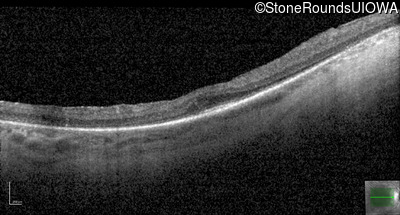

Optical Coherence Tomography - Left - 20/50 -2

Exemplar / OCT Stack

OCT Stack